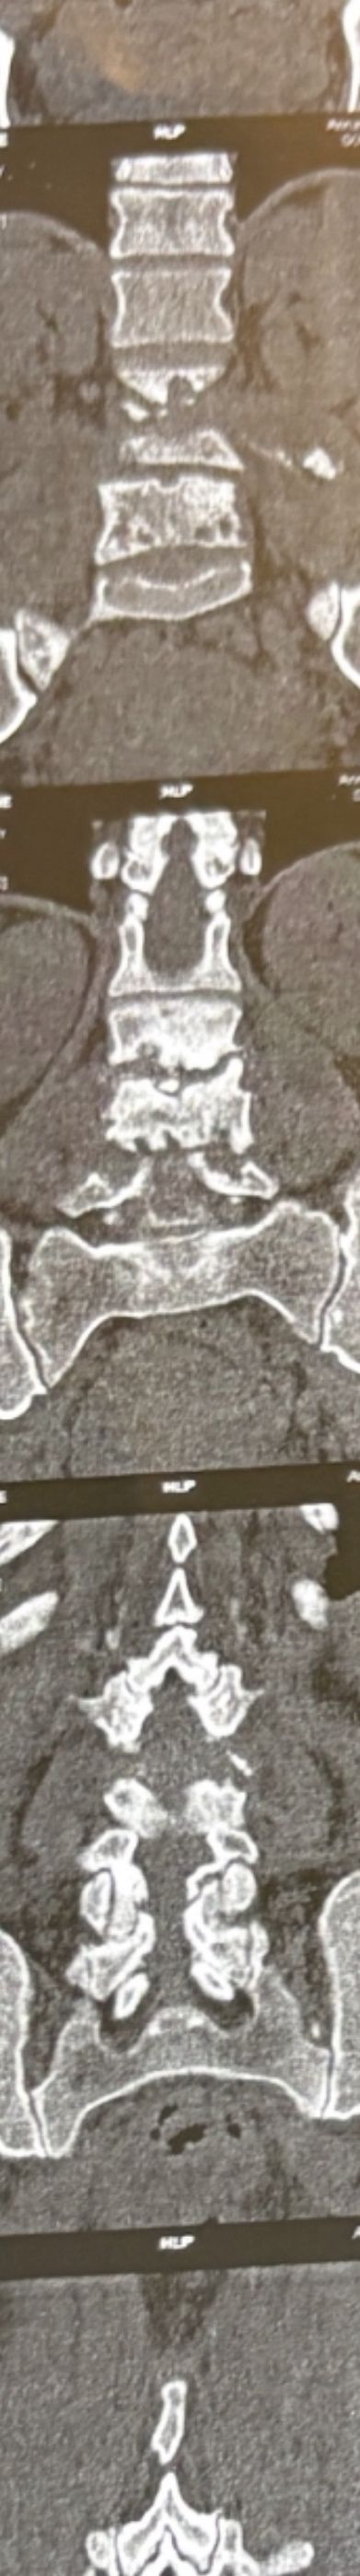

Case 4

41 years old man presented to my clinic in October 2023 with acute and sever R neck pain with radicular pain to his R upper extremity along C6 dematom since 2 weeks ago. Examination didn’t show any upper motor signs. Was suggested urgent surgery

I ordered EMG/ NCV : showed mild R C6, C7 irritation without any active axonal loss

In his MRI was reported R. para R. IVF Massive extrusion. I decided to control his pain and manage this patient with reevaluation of patient every other session. For 5 sessions i just used acupuncture and laser and IFC and mild adjustments to his R. T3-T7 and mild arthosteem to above and below involved segment. Cervical adjustment considered contraindicated for this patient. From session 6th- 8th i started to use mild/gentle cervical decompression. He used soft cervical collar all the time. His pain decreased by 80 percent

I gave him cervical traction pump to be used 3-5 times per day at home for the next 3 months and i released the patient. He was evaluated every week once for one month and after that every 2 weeks. After 3 month I repeated MRI. Size of the herniated disc was reduced greater than 50 percent. Asked him to do another mri in 6 months

MRIs before and after proper management of this patient: